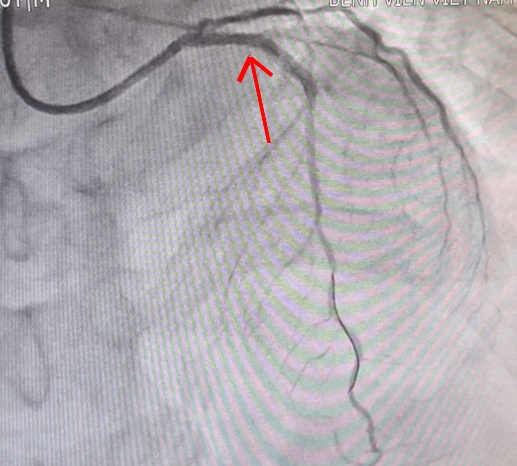

Mạch vành của người bệnh trước và sau khi can thiệp. |

Các bác sĩ đã chụp mạch vành xâm lấn qua da để đánh giá mức độ tổn thương và kịp thời can thiệp cho người bệnh. Kết quả cho thấy người bệnh có tổn thương nặng ba thân động mạch vành, trong đó có nhánh động mạch vành trái bị tắc cụt hoàn toàn…

Theo các bác sĩ khoa Nội tim mạch, đây là trường hợp nhồi máu cơ tim rất phức tạp, hẹp cả 3 thân động mạch vành chính gây thiếu máu nuôi dưỡng cho tim, nguy cơ tử vong rất cao.

Các bác sĩ đã nhanh chóng đặt stent động mạch vành trái cho bệnh nhân. Sau thời gian điều trị, người bệnh đã hồi phục và được ra viện trong niềm vui, phấn khởi của gia đình.